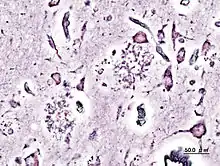

La nueva variante de la enfermedad de Creutzfeldt-Jakob (nvCJD) es un mal neurológico con formas genéticas hereditarias y también contagiosas, producidas por una proteína llamada prion (PrP) que se pliega de forma anómala; dicha alteración en la conformación de la estructura de la PrP provoca la muerte neuronal y, por tanto la destrucción de masa encefálica, especialmente en el tálamo. Más adelante, la enfermedad cursa con proliferación glial. Ambos hechos proporcionan un aspecto espongiforme a los encéfalos afectados.

Para su diagnóstico se emplean técnicas de inmunohistoquímica con anticuerpos monoclonales específicos, o, en casos graves, simplemente tinciones de rutina. Se muestrea mediante biopsia de la corteza, núcleos basales o tálamo.